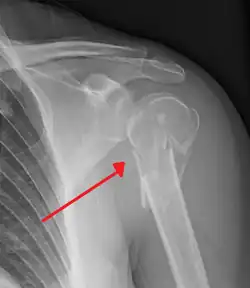

The axillary nerve is located at the proximal end, against the shoulder girdle. Dislocation of the humerus's glenohumeral joint has the potential to injure the axillary nerve or the axillary artery. Signs and symptoms of this dislocation include a loss of the normal shoulder contour and a palpable depression under the acromion.

Fracture of the proximal humerus -